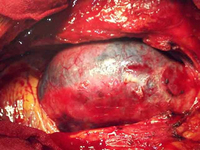

Dissection status post proximal repair with late distal aneurysm

From the collection of Dr Eric E. Roselli; used with permission